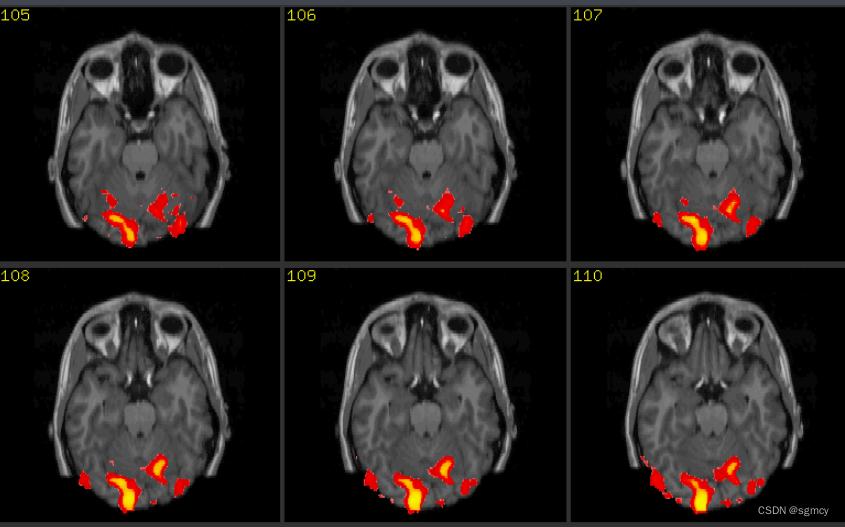

来源:CSND

第二种是非侵入式脑机接口,这就很好理解了,不会直接接触大脑皮层,仅通过头皮采集脑电信号。但以这种方式采集到的信号纯度不高,而且还会伴有大量的噪音。